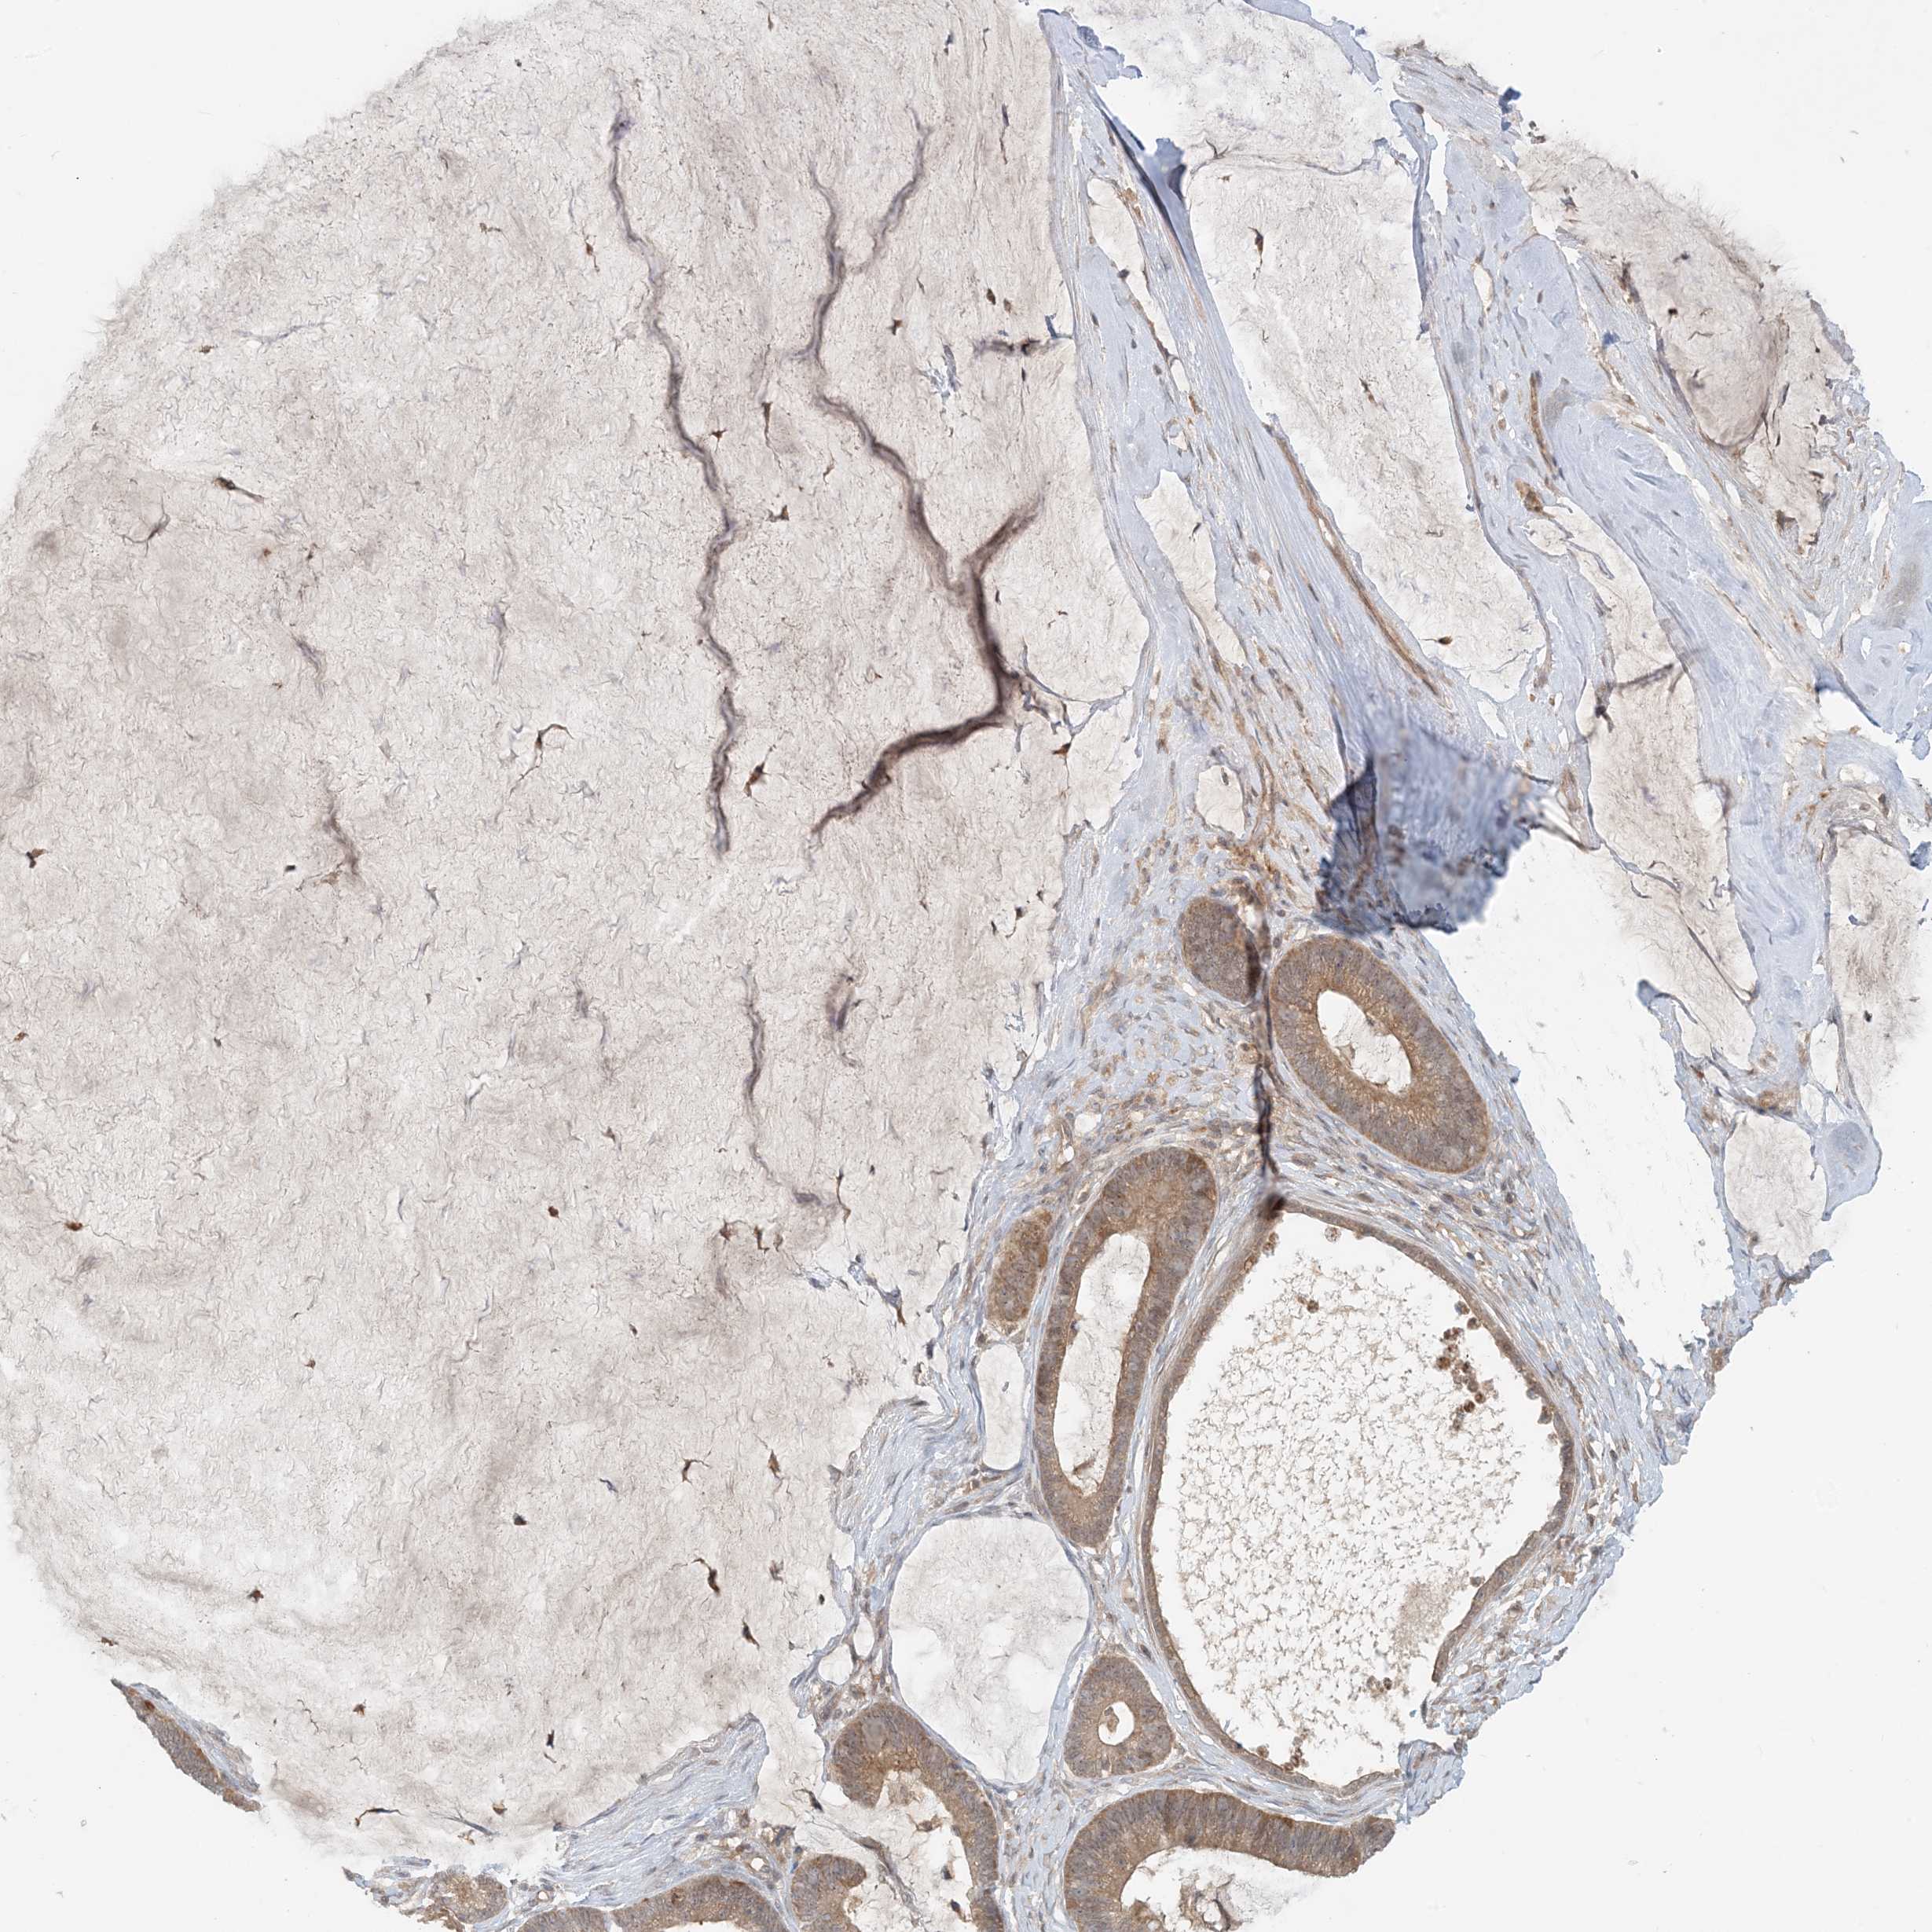

OVARIAN CANCER - Protein expressioni

A mouse-over function shows sample information and annotation data. Click on an image to view it in a full screen mode. Samples can be filtered based on level of antibody staining by selecting one or several of the following categories: high, medium, low and not detected. The assay and annotation is described here.

Note that samples used for immunohistochemistry by the Human Protein Atlas do not correspond to samples in the TCGA dataset.

Antibody stainingi

Antibody staining in the annotated cell types in the current human tissue is reported as not detected, low, medium, or high, based on conventional immunohistochemistry profiling in selected tissues. This score is based on the combination of the staining intensity and fraction of stained cells.

Each image is clickable and will lead to virtual microscopy that enables deeper exploration of all samples and also displays staining intensity scores, fraction scores and subcellular localization as well as patient and tissue information for each sample.

Antibody HPA034785

Antibody HPA034786

Staining

High

Medium

Low

Not detected

Intensity

Strong

Moderate

Weak

Negative

Quantity

>75%

75%-25%

<25%

None

Location

Nuclear

Cytoplasmic/membranous

Cytoplasmic/membranous,nuclear

Cystadenocarcinoma, mucinous, NOS